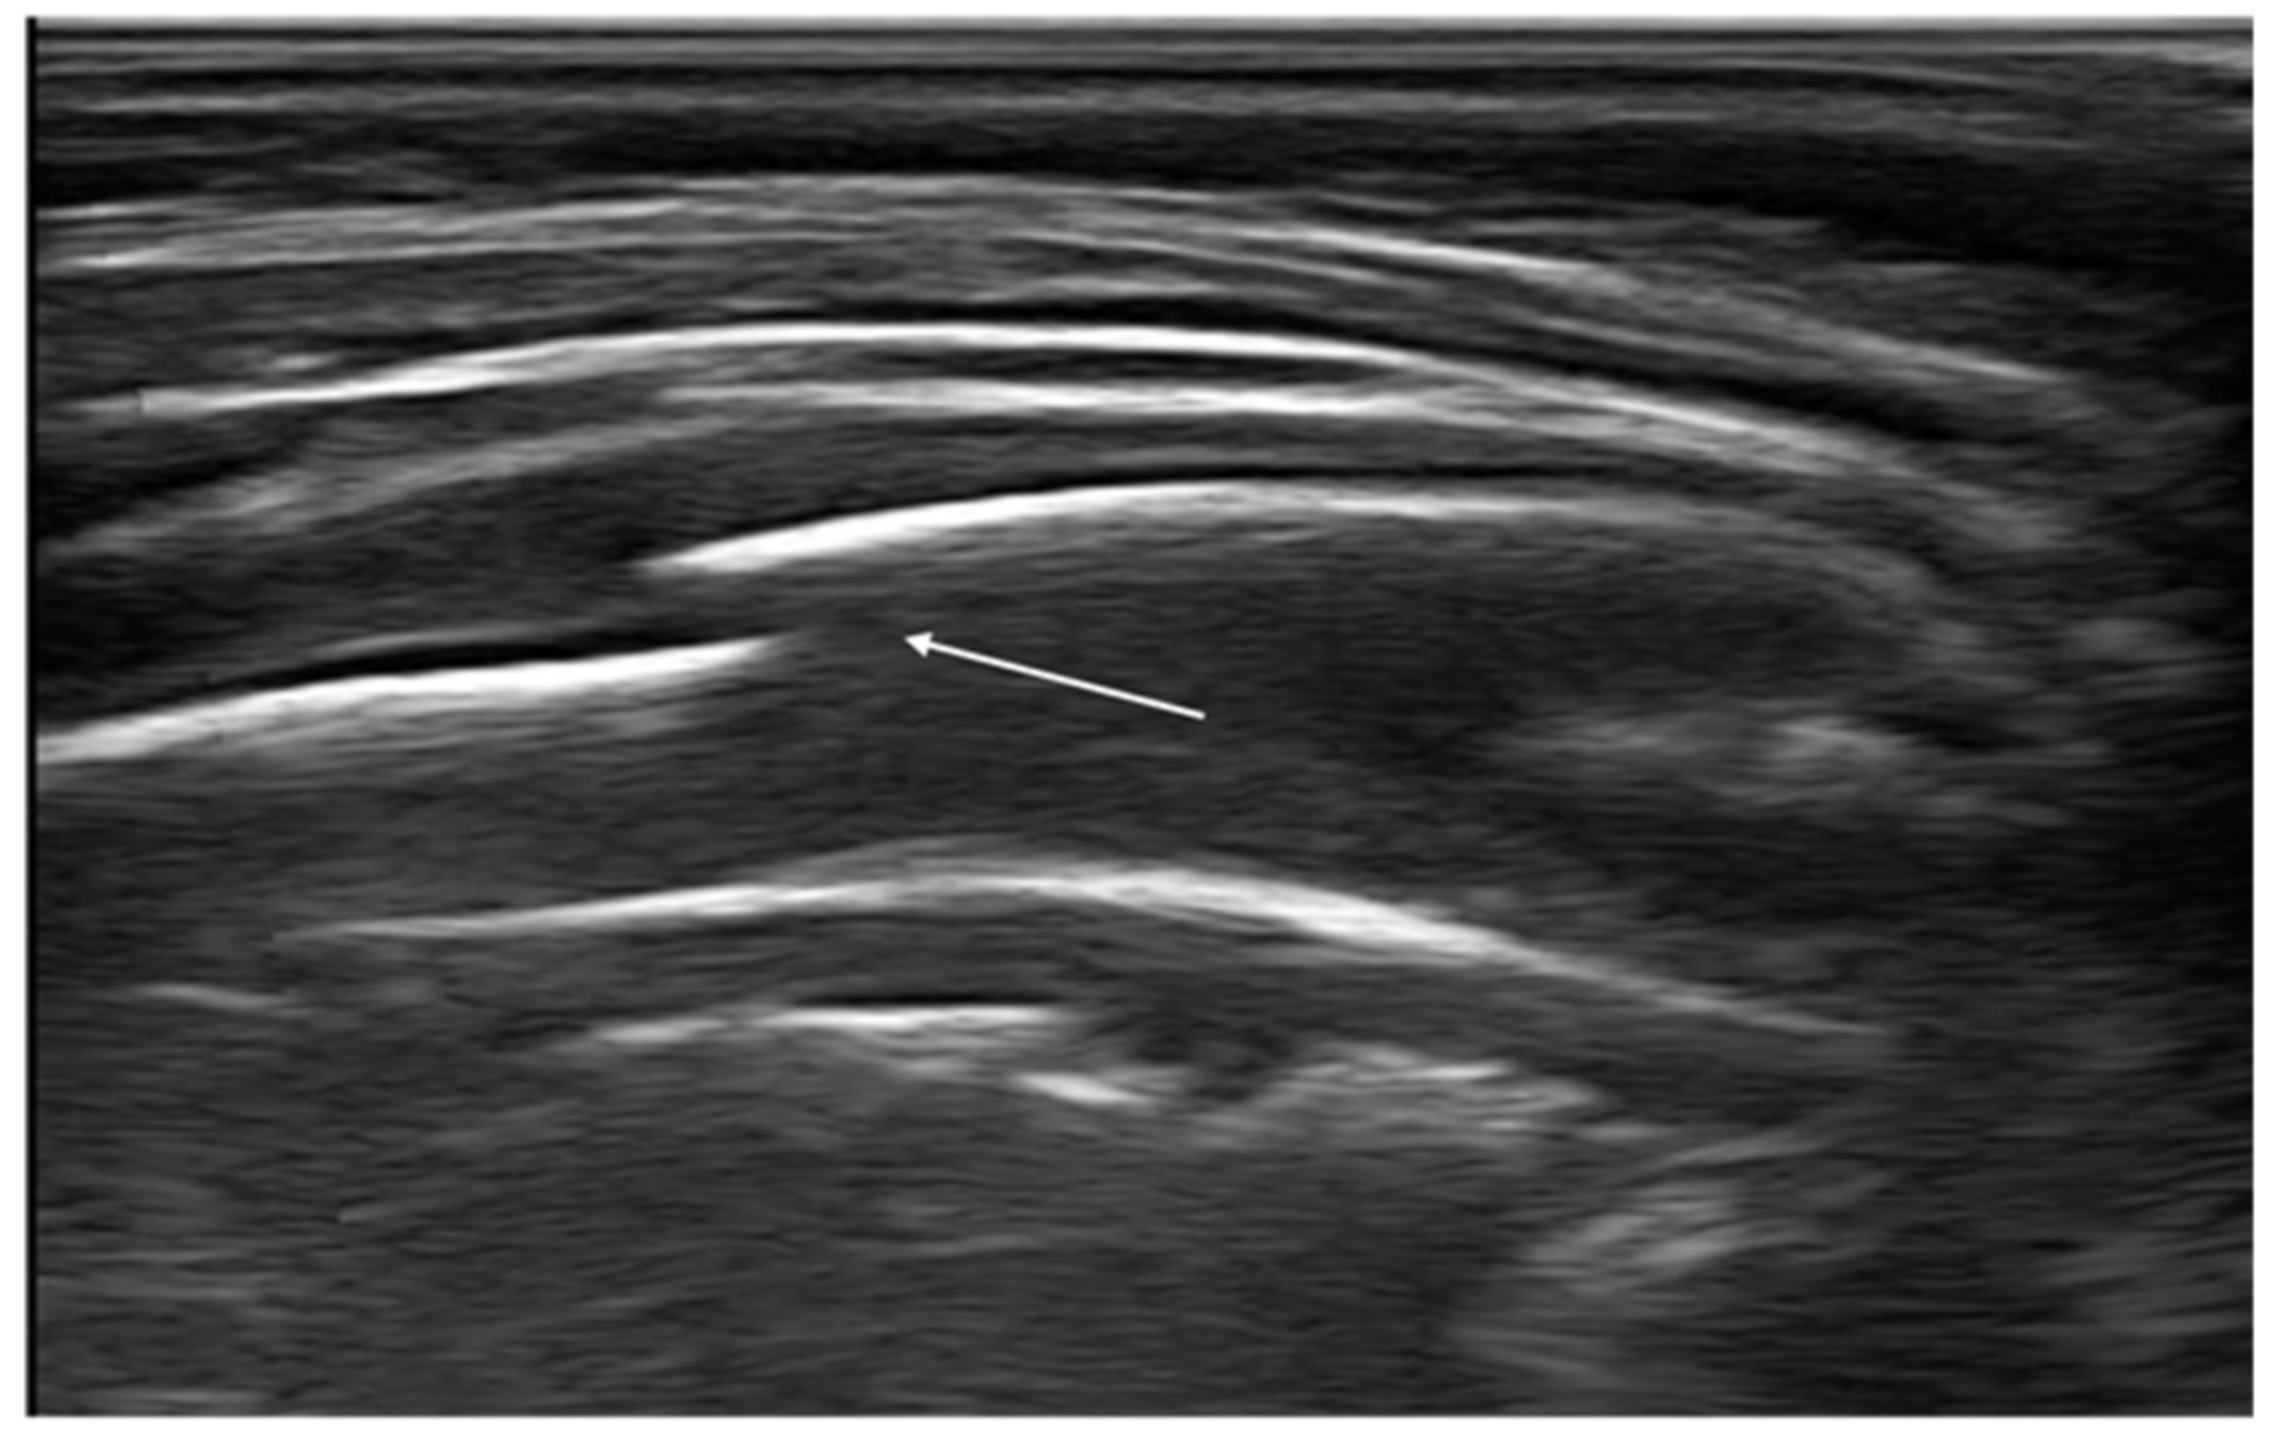

Another sonographic artifact is represented by the “Z-lines”. These artifacts are formed by reverberation echoes from irregularities on the lung surface and appear as vertical echogenic lines (but less echogenic than a pleural line) originating from the pleura that does not erase the A-lines and do not move with lung sliding (Figure 2) [16]. These should be distinguished from B-lines that are similar to Z-lines but usually indicate the presence of fluid in the interstitial compartment or, in general, an abnormality in the alveolar or interstitial compartment. B-lines appear as a vertical line arising from the pleura, often erasing the A-lines and moving with the lung sliding (Figure 3) [16].

Figure 2. Isolated Z-lines (white arrow).